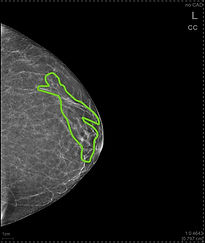

Notice how these are images from 3 different patients. They all have breasts with more WHITE glandular tissue, and not as much GRAY breast fat.

These women have DENSE breast tissue. The areas of white are outlined below, just to be very clear about which part is the glandular tissue.